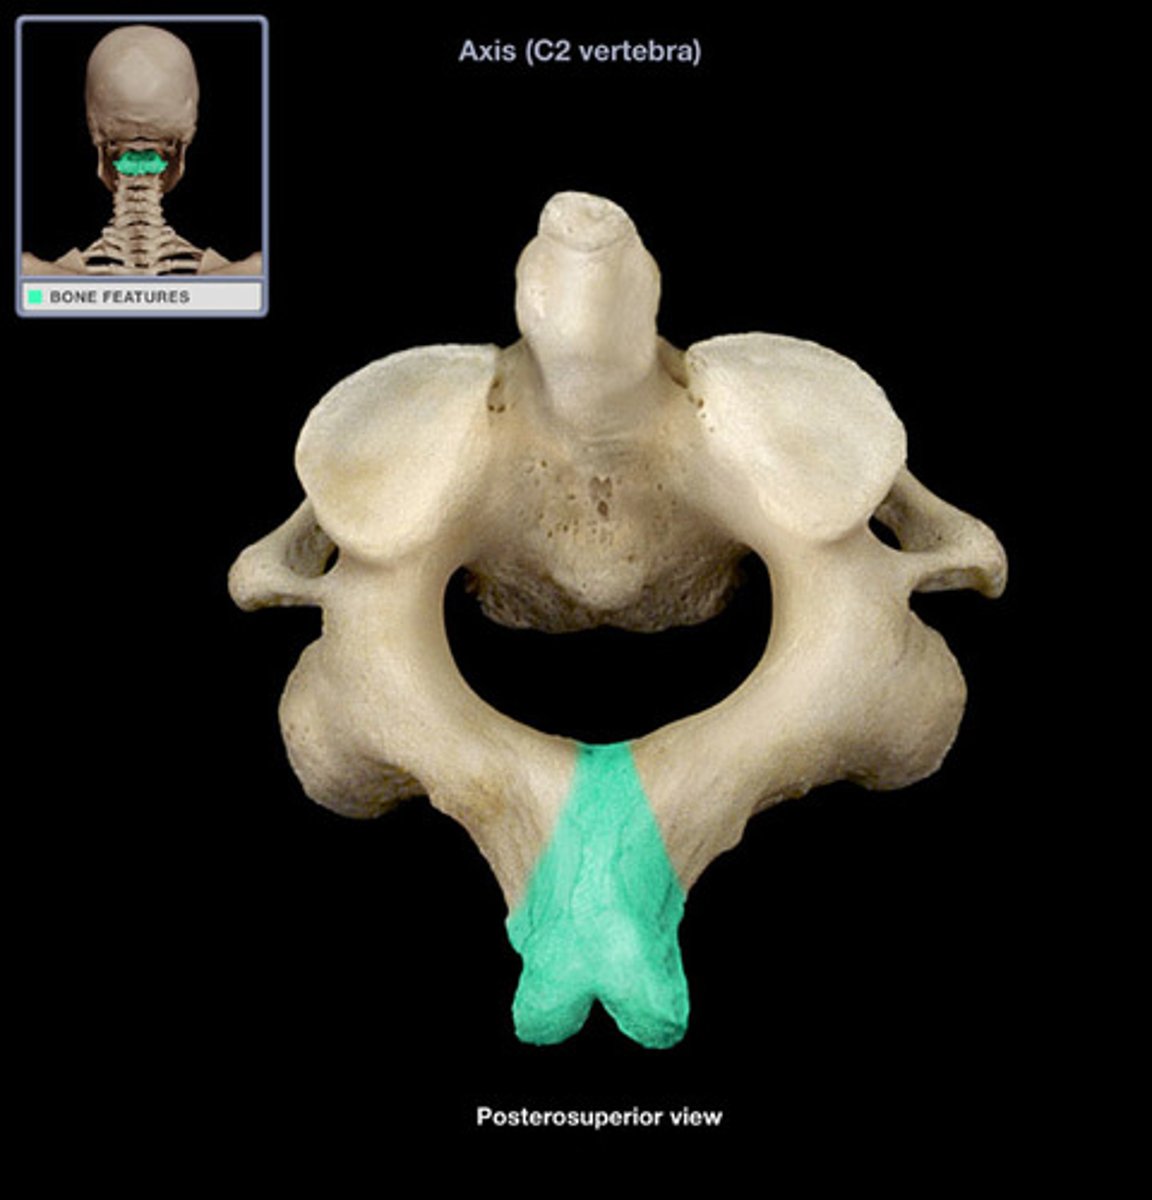

axis C2

C2

what vertebra is considered the axis

what structure allows for head rotation in C2

adontoid process (dens)